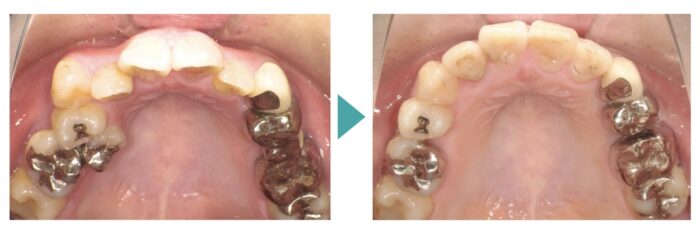

患者さま:40代女性/右上4・5・6番にメタルブリッジ

主訴:歯並びのガタガタが気になる

年齢と銀歯がたくさん入っているので、矯正できるか気にされていました。ブリッジの部分の歯根状態に問題がなかったのでブリッジはそのまま、マウスピース矯正装置(インビザライン)で矯正治療を行いました。

歯並びの矯正が終わり、整った口元になったことで、今度は銀歯が少し気になるようになったそうです。せっかく綺麗になった歯並びをより自然に見せたいとのことで、今後は少しずつセラミックの白い歯に置き換えていく予定です。

- 【症例詳細】

- 主訴:ガタガタが気になる

- 診断名:叢生

- 初診時年齢:49歳

- 使用装置:マウスピース矯正装置(インビザライン)

- 抜歯部位:なし

- 治療期間:1年2ヶ月

- 費用:¥865,000(税込¥951,500)

- リスク・副作用:痛み、歯根吸収、歯肉退縮、むし歯、後戻り